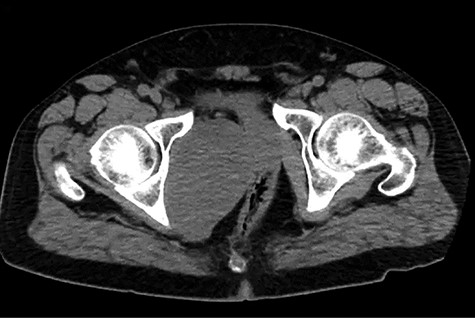

A healthy 47-year-old male with past medical history significant only for hypertension and nephrolithiasis presented to Englewood Health Medical Center in October 2019 with right flank pain radiating to the pubis, hematuria, hard stool with straining and fifteen pound weight loss over 6 months. On physical examination, multiple café au lait spots, small neurofibromas on his trunk and arms and axillary and inguinal freckling were observed. On CT scan, he was found to have a 10.1-cm soft tissue mass in the right hemipelvis and a nephroureteral stent with a 3-mm stone in the proximal right ureter (Fig. 1). Further history revealed the patient had a known pelvic mass discovered on CT approximately 10 years prior (Fig. 2), which was again observed on CT in June 2019 during a hospitalization for nephrolithiasis at Hackensack University Medical Center (Fig. 3); he had been lost to follow-up.

HUMC CT 11/14/09: 3.3 × 6.6 × 3.0-cm-sized right pelvic wall soft tissue mass.